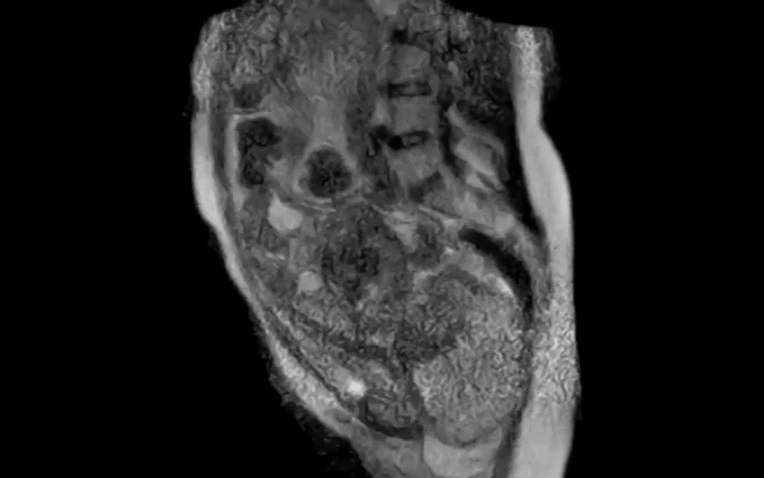

Quay lại với ca sinh nở, các nhà khoa học tại Bệnh viện Đại học Charité, Berlin, Đức đã ghi lại 45 phút cuối của quá trình chuyển dạ, sau đó rút gọn thành một đoạn video dài 25 giây. Hình ảnh cho thấy rõ vị trí thai nhi, sự di chuyển của em bé qua ống sinh và sự thay đổi của các cơ quan trong cơ thể người mẹ khi rặn sinh.

Theo nhóm nghiên cứu, trước đó hiểu biết về cơ chế sinh nở chủ yếu dựa trên giả định và các nghiên cứu X-quang đã cũ. Việc quan sát trực tiếp bằng MRI giúp bác sĩ hiểu rõ hơn quá trình này, đặc biệt hữu ích trong những ca sinh khó.